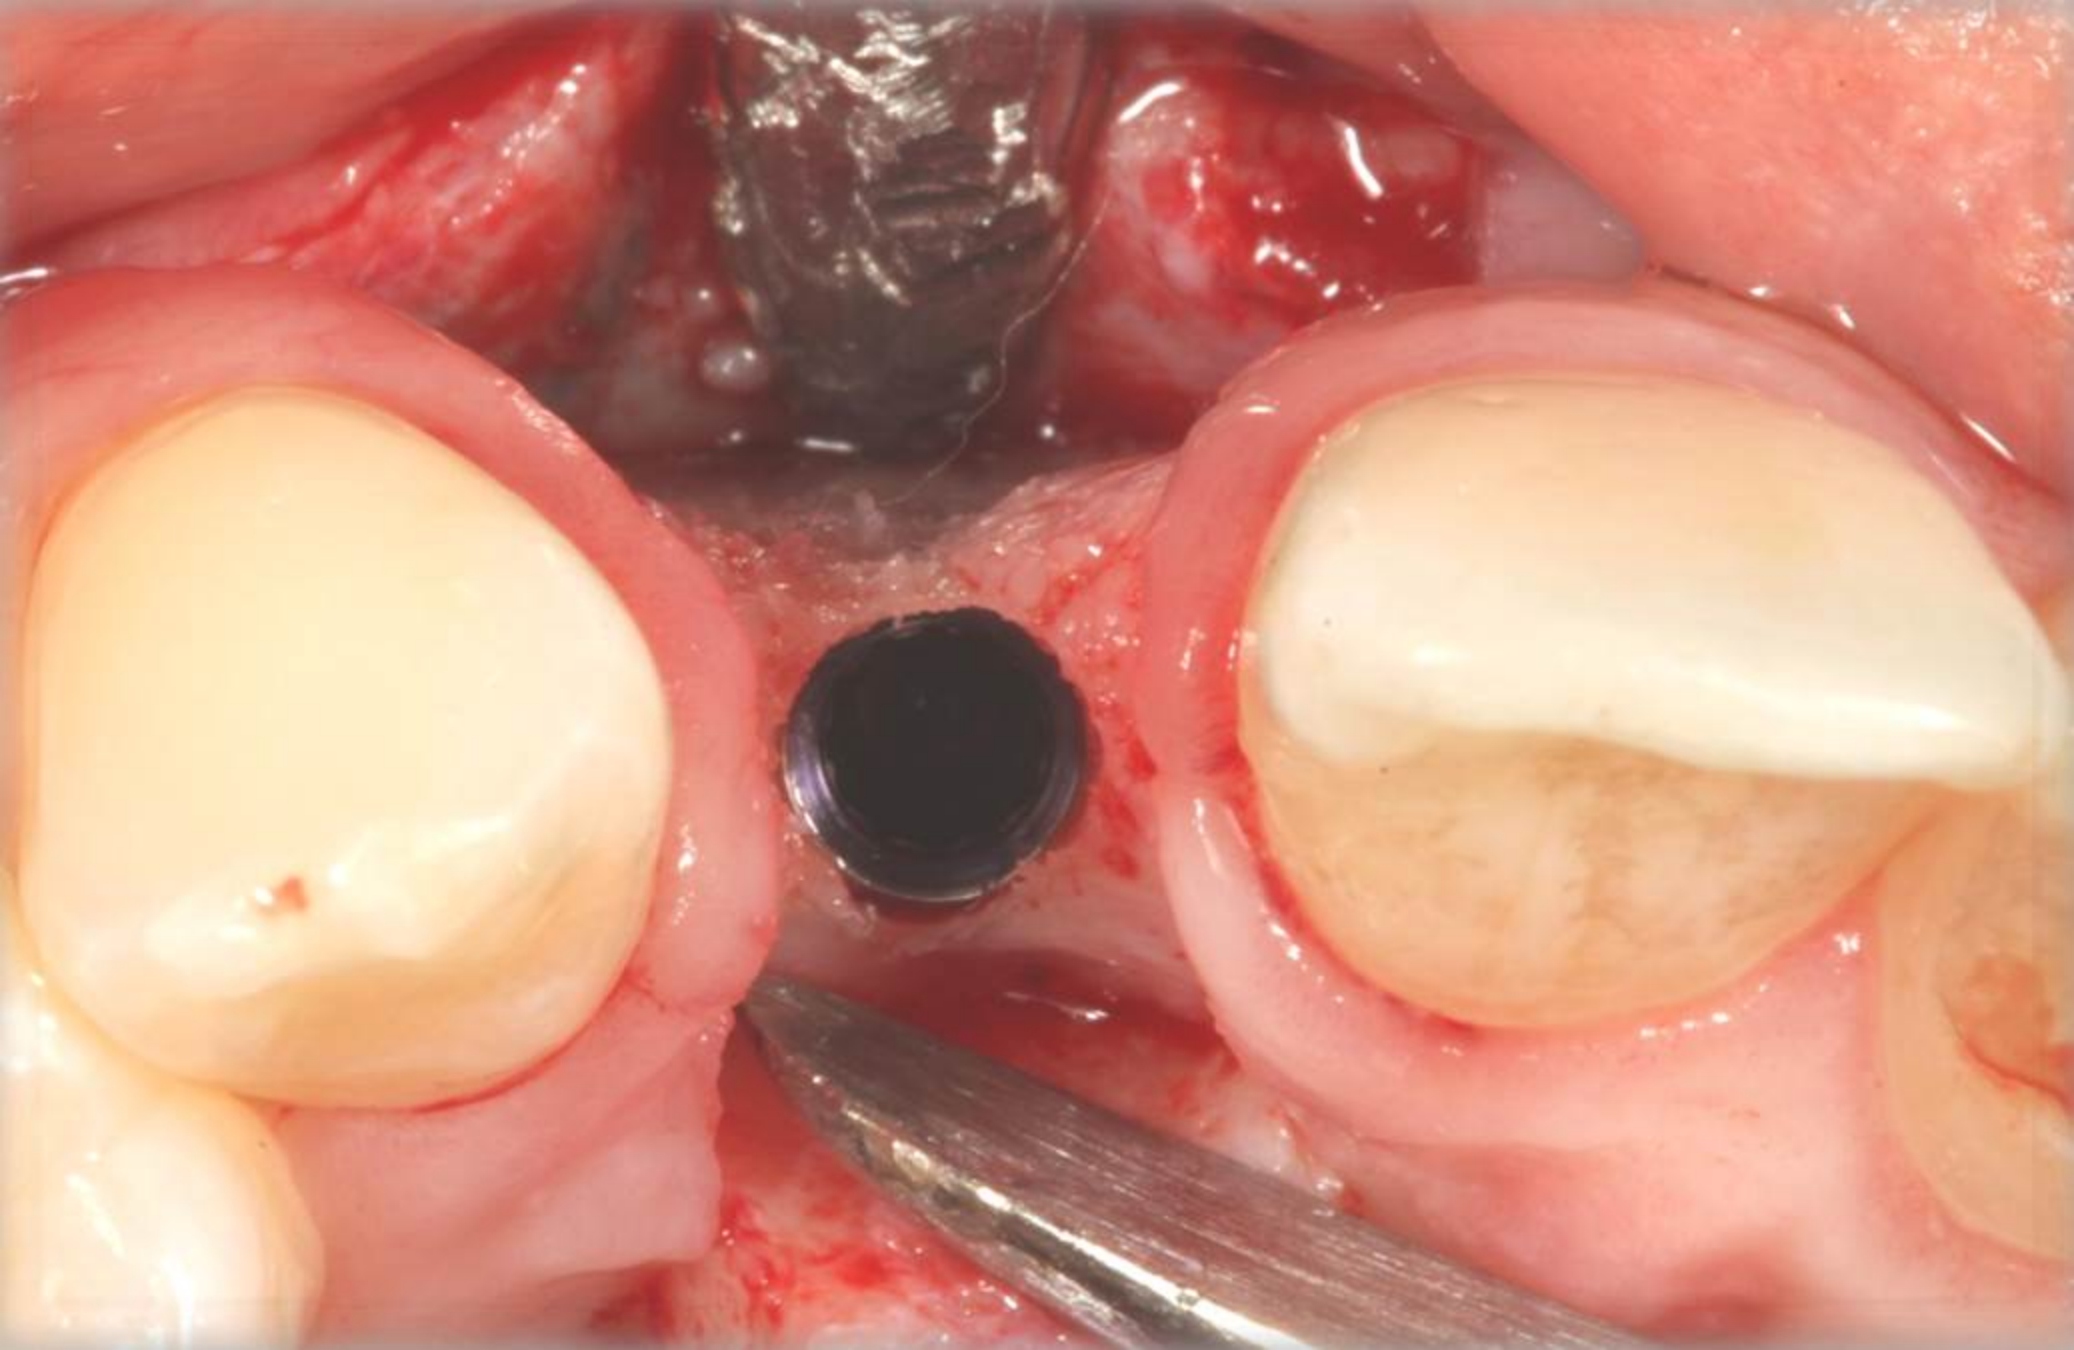

Fig 7. Vertical releasing incisions sutured to attain primary closure, buccal view.

Figure 7

Fig 8. Submerged implant protocol, occlusal view. A horizontal releasing incision was sutured to attain primary closure. Note that there are no sutures through the thin retained papillary segments.

Figure 8